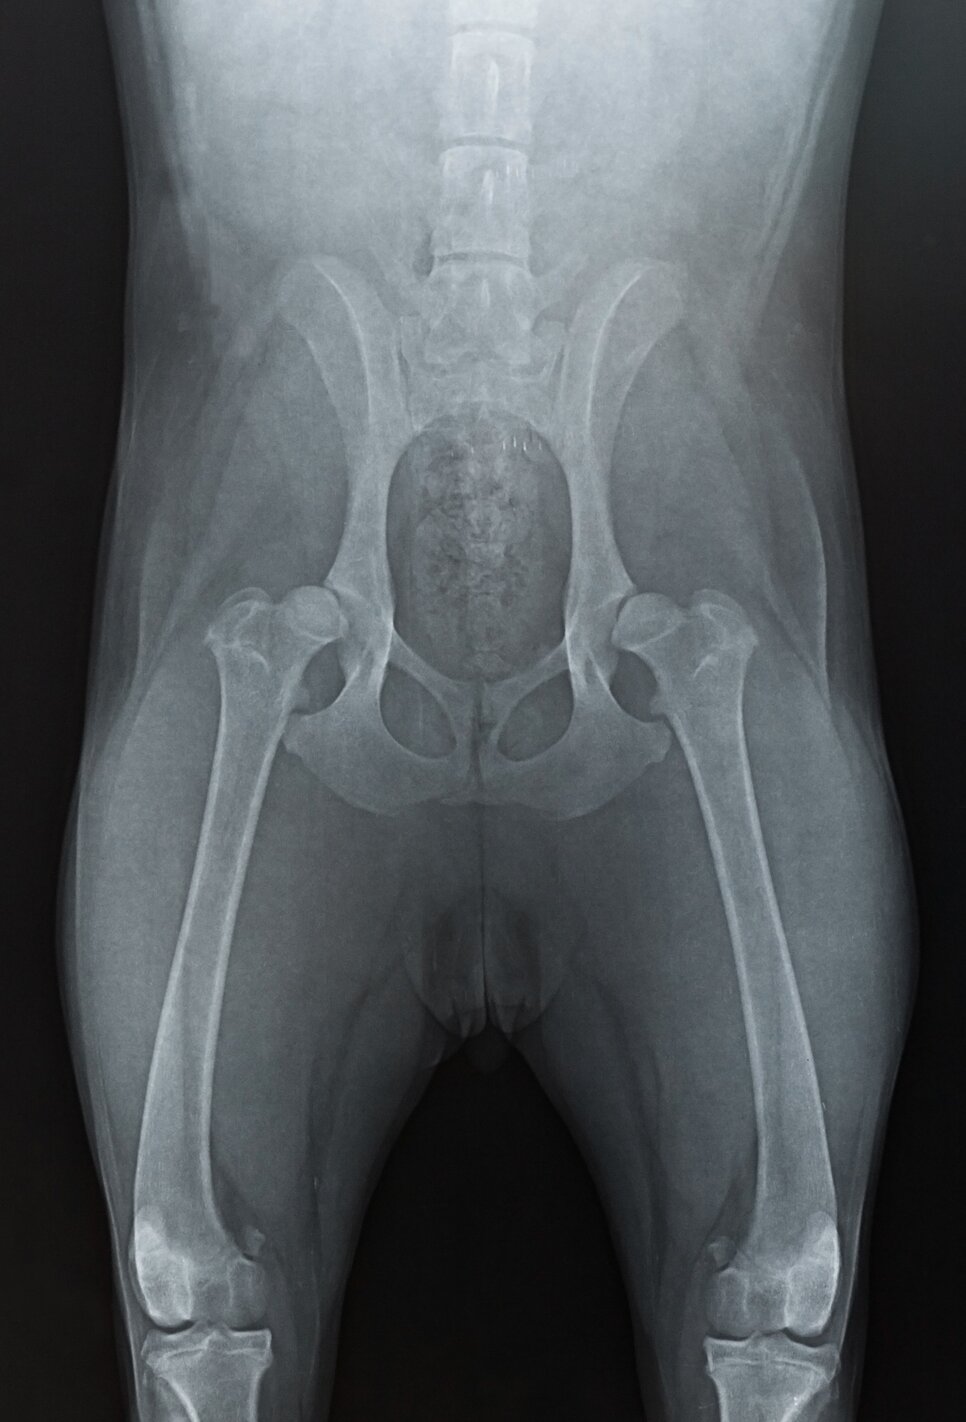

Diagnosis of hip dysplasia requires a veterinary examination. Your veterinarian will be able to watch your dog walking and observe for any abnormalities in their gate, physically examine your dog, test the range of their hip extension, and complete radiographs (xrays).

Radiographs are an essential part of the diagnosis of of hip dysplasia in dogs. Hip xrays usually require sedation to allow your vet to fully extend your dog's hips in a quick and painless way, so many dog owners choose to have diagnostic xrays done at the time as desexing. This means your dog will only need to be sedated once. However, there is also some evidence to suggest that desexing later in life may help the hips develop properly, so it's important to weigh up all your options.

Based on the radiographs, your veterinarian will be able to assess the depth of the acetabulum and the shape of the femoral head, and will form a grade of your dog's hips.